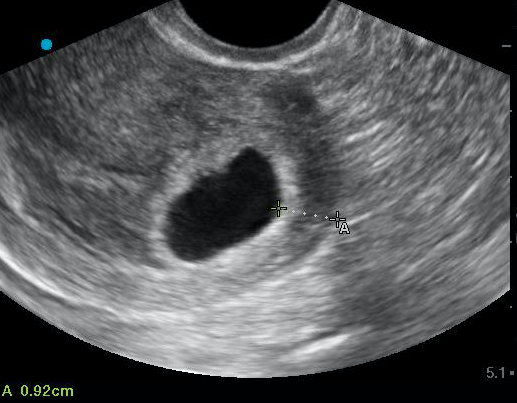

In our case, the endomyometrial mantle was measured at 9.2mm (Figure 5). The patient was counseled closely on return precautions and expectant management. She was started on prenatal vitamins and scheduled for a follow up appointment with her obstetrics provider in the next several days as an outpatient.

Take your early pregnancy ultrasound to the next level— measure the endomyometrial mantle to assess for the possibility of interstitial ectopics. Values >8-9mm are considered normal and safe for discharge home.